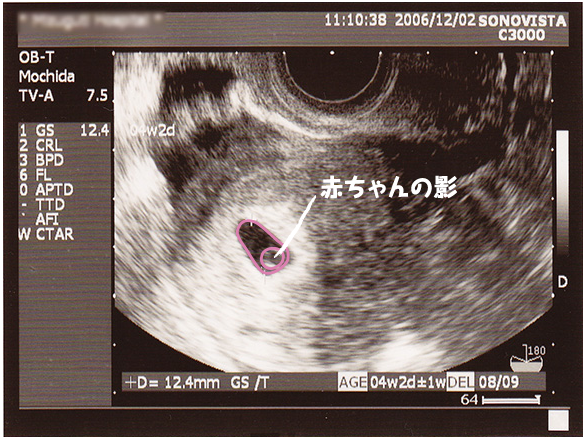

妊娠2ヶ月 妊娠4週 5週 6週 7週 妊娠初期 の超音波写真 妊娠 出産 育児に関する総合情報サイト ベビカム

妊娠4週目 4w0d 6d のエコー写真とエピソード 妊娠2ヶ月 Cozre コズレ 子育てマガジン

妊娠4週目のエコー写真 胎芽や胎嚢 初期症状や流産のこと 妊娠初期 All About

妊娠2ヶ月 妊娠4週 5週 6週 7週 妊娠初期 の超音波写真 妊娠 出産 育児に関する総合情報サイト ベビカム

妊娠4週 赤ちゃんのエコー写真 超音波写真まとめ たまひよ